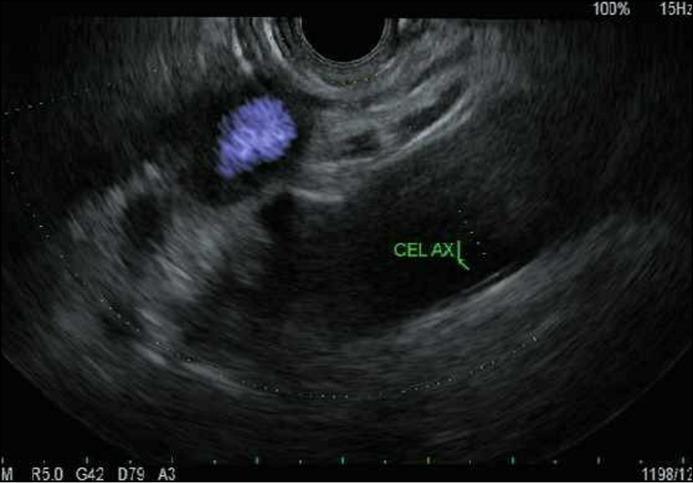

A 46-year-old female with no previous personal or family psychiatric history underwent endoscopic ultrasound (EUS)-guided celiac plexus blockade (CPB) to treat pain related to cystic fibrosis transmembrane conductance regulator-associated chronic pancreatitis. She had excellent response to her first three CPBs using bupivacaine and triamcinolone. The patient's subsequent CPBs were complicated by symptoms of racing thoughts, delusional thinking, and insomnia. She was diagnosed with acute psychosis secondary to triamcinolone. This is the first reported case of steroid-induced psychosis caused by EUS-guided CPB. Optimal treatment for steroid-induced psychiatric symptoms include dose reduction or discontinuation of steroids and administration of lithium, valproic acid, or atypical antipsychotics.

一名46岁女性,既往无个人或家族精神病史,接受了内镜超声(EUS)引导下的腹腔神经丛阻滞(CPB)以治疗与囊性纤维化跨膜传导调节因子相关的慢性胰腺炎引起的疼痛。她对前三剂使用布比卡因和曲安奈德的CPB反应良好。该患者随后的CPB出现了思维奔逸、妄想思维和失眠症状。她被诊断为曲安奈德继发的急性精神病。这是首例关于EUS引导下CPB导致类固醇诱导性精神病的报道病例。类固醇诱导性精神症状的最佳治疗方法包括减少或停用类固醇以及给予锂盐、丙戊酸或非典型抗精神病药物。